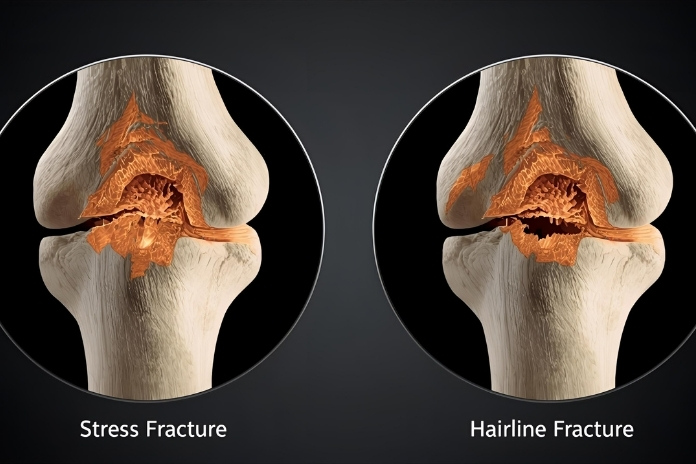

Two such examples are stress fractures and hairline fractures. Although they sound and have some symptoms in common, and are often used interchangeably, they differ in the way they occur, feel, and heal.

Key Differences Between Stress and Hairline Fractures

Though we often interchange stress and hairline fractures, they vary in a few aspects. Despite both having microcracks in the bone, the mechanisms, pain patterns, and healing are quite different from one another. Once you know the differences, it can help you get the appropriate treatment to feel better soon.

1. Cause

Stress Fracture: It occurs due to repetitive overuse or constant pressure. The common causes include running long distances, sudden peaks in training intensity, or improper footwear. Insufficient calcium intake and endocrine abnormalities can also decrease bone resilience.

Hairline Fracture: This happens due to a single traumatic event, like a fall, direct blow, or twist. The fracture occurs immediately rather than gradually building up.

2. Onset of Pain

Stress Fracture: The pain gradually increases, typically slow at first, and later worsens with increasing activity. The pain can resolve with rest, but recur and worsen if we keep repeating the movement.

Hairline Fracture: There is pain and tenderness immediately after the injury. However, you’ll see that the swelling or bruising usually happens over a few hours.

5. Recovery and Healing

Stress Fractures: These fractures can recover in 8–12 weeks because such bones tend to absorb load even when resting.

Hairline Fractures: These heal slightly faster, about 6–8 weeks, provided the bone is kept immobilized and not subjected to further stress.